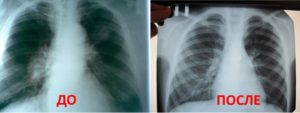

Для обнаружения легочных заболеваний в первую очередь используется флюорография. Эту процедуру необходимо проводить ежегодно, в основном она направлена на выявление ранней стадии туберкулеза. Однако опытный рентгенолог может выявить на снимке образовавшиеся плевральные спайки, которые выглядят тенями. Причем форма их не меняется в зависимости от вдоха и выдоха.

При необходимости дополнительно назначается рентген. Как правило, спайки располагаются в нижней части легкого. При этом будет более темная картинка, а также может быть частичная деформация грудной клетки и диафрагмы.

Самым распространенным методом диагностики легких является – флюорография. Но если врач подозревает, что у пациента есть спайки, то больной отправляется на рентген. По рентгеновскому снимку распознать синехию можно по мутным темным пятнам. Она выглядит, как теневое затемнение и неподвижна при вдохе и выдохе.

Плевродиафрагмальная спайка на снимке рентгена

Иногда выявляется деформация грудной клетки и диафрагмы. Чаще всего спаечный процесс отмечается в нижней части легкого. Такой вид спаек – плевродиафрагмальный, а вид спаек в верхней части – плевроапикальный.